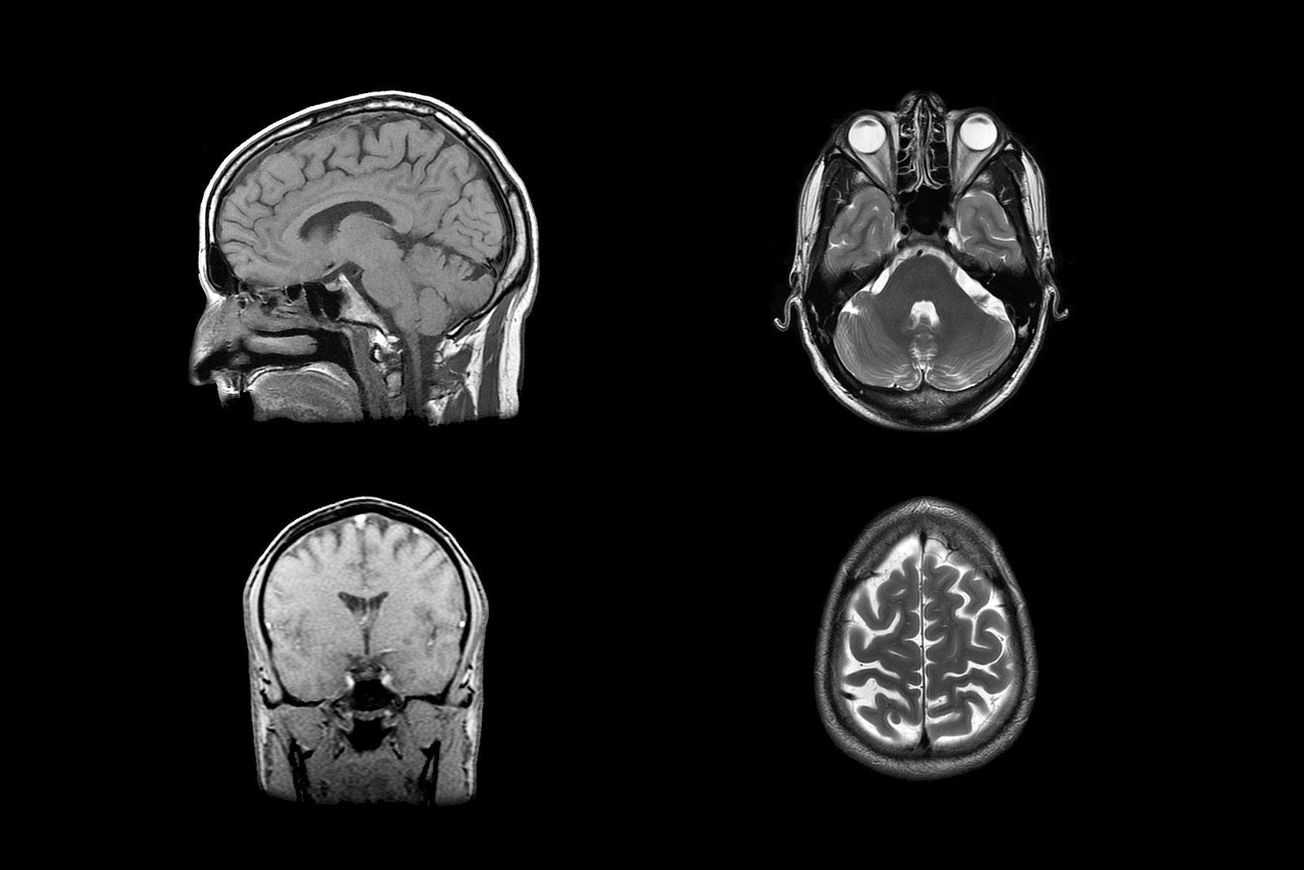

Currently, practitioners diagnose brain tumours through initial neurological exams, such as testing vision, hearing, coordination and reflexes. Imaging tests are also commonly used, such as magnetic resonance imaging (MRI) and computerised tomography (CT) scans. Biopsies can be taken during brain operations, however such invasive procedures are accompanied by higher risks.

Featured image: Flickr / David Foltz